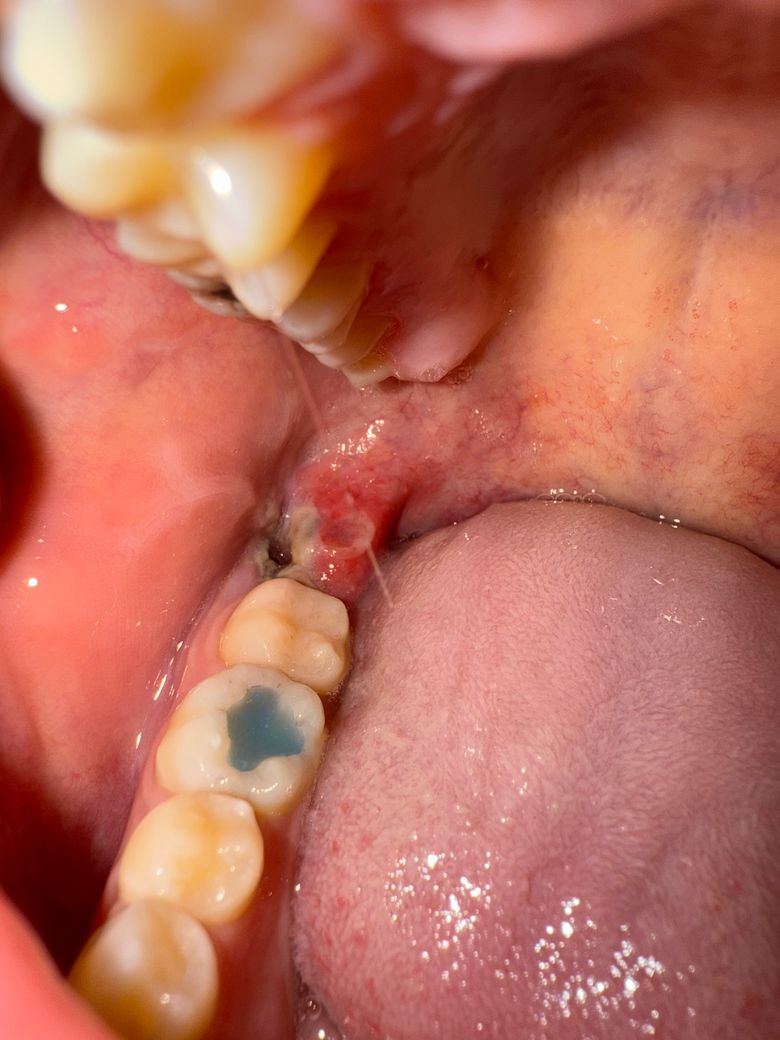

일반 사랑니 발치 5일차 미봉합입니다

잇몸이 조금 부었는데 잘 회복중인거 맞나요?? 아니면 드라이소켓 의심해 봐야하나요? 회복이 더딘거 같아서 약간의 걱정이 듭니다.

사랑니 발치를 한부위 잇몸이 부어서 그러는거니 최대한 자극만 가지 않도록 해주시는게 좋습니다.

드라이소켓보다는 염증이 다소 있네요 치과에서 발치 후 처방해준 약 잘 복용하시기 바랍니다.